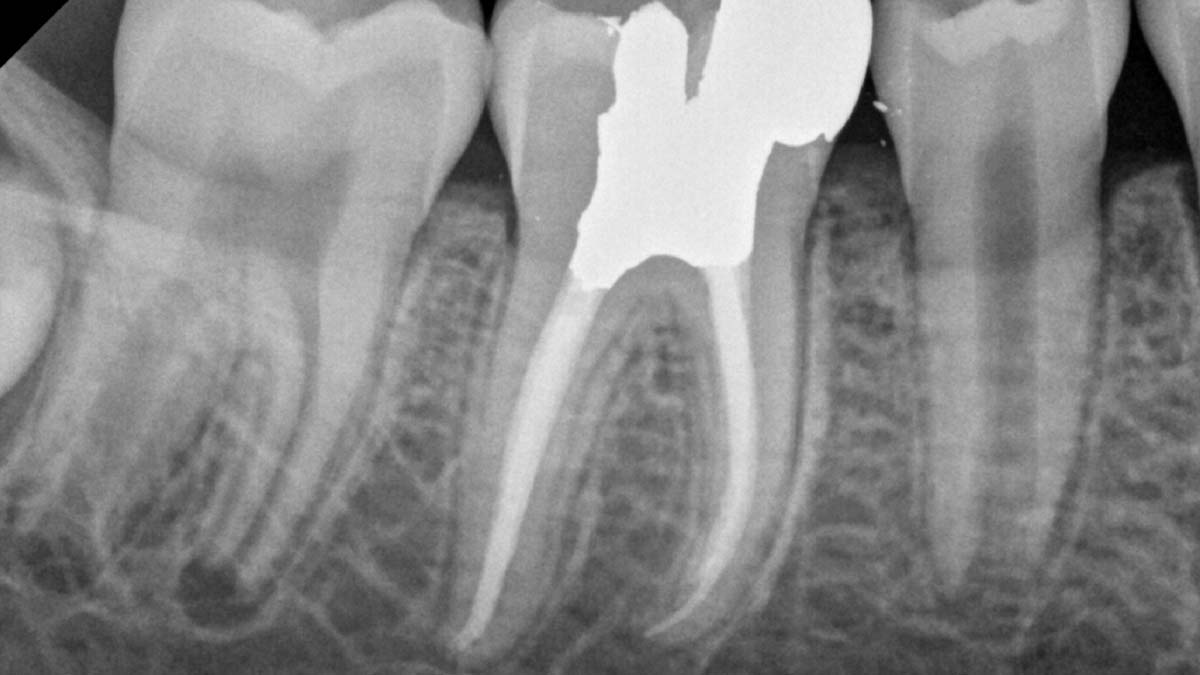

Po lewej: Stosowanie różnych formuł gutaperki w jednym przypadku może powodować różne stopnie nieprzezroczystości.

Zdjęcie dzięki uprzejmości dr Phillipa Bella, Mooresville, NC